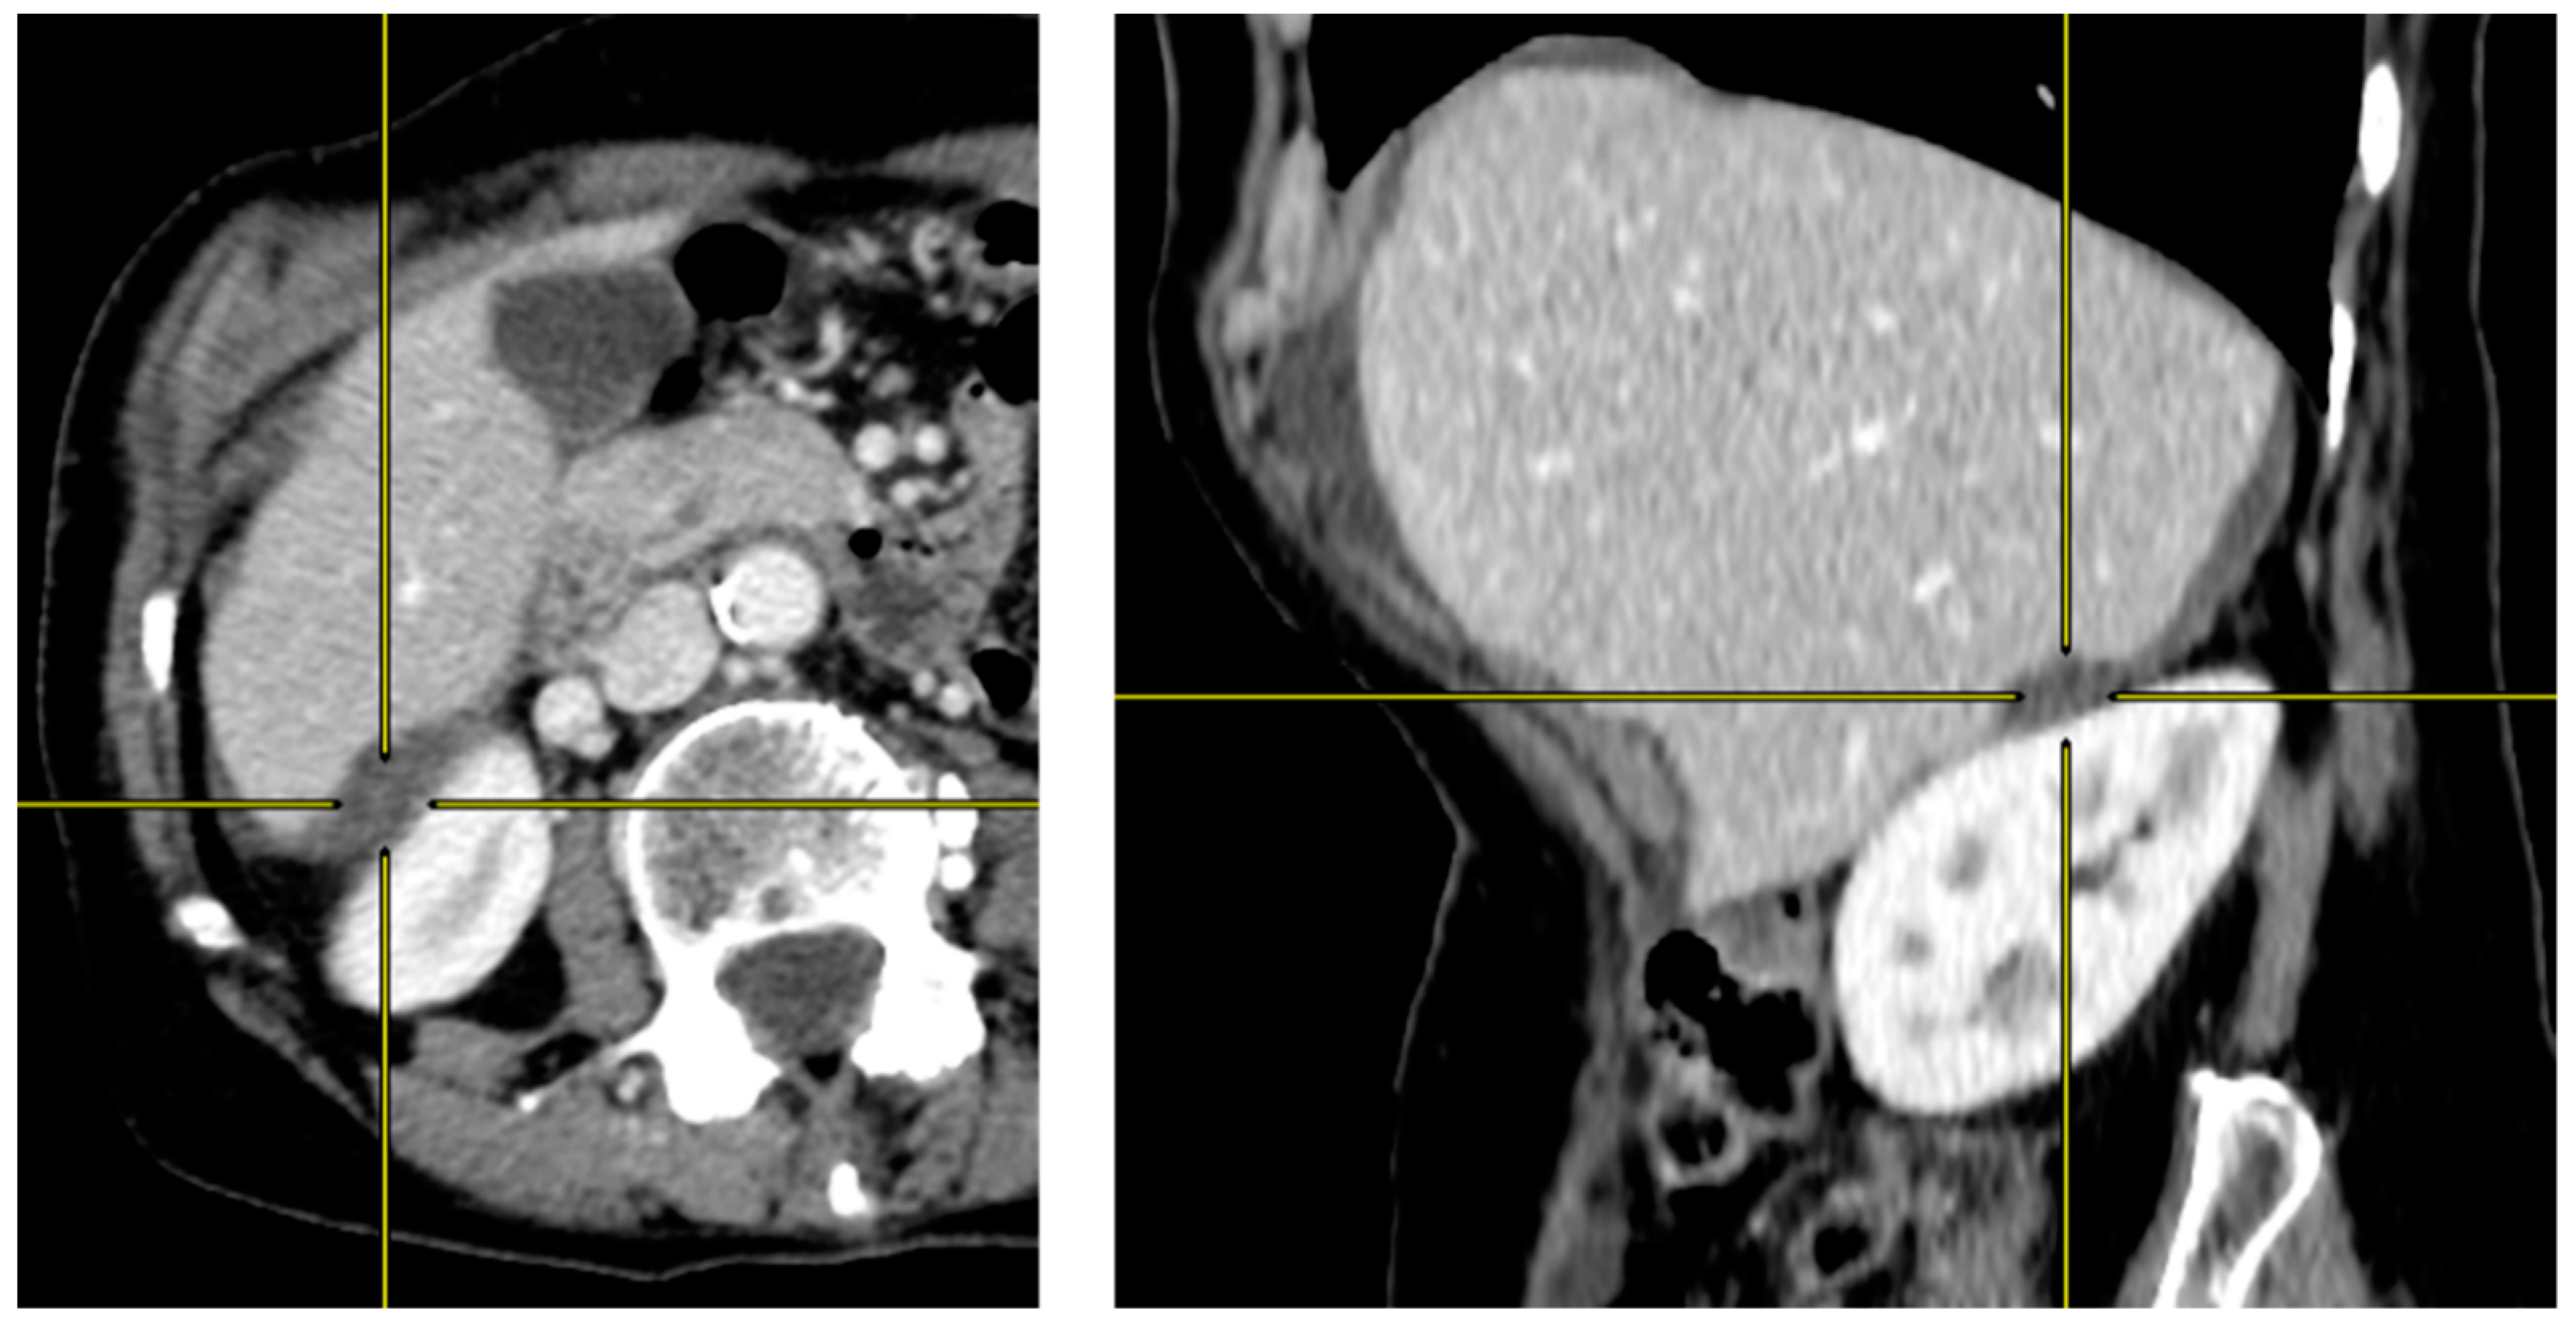

2.2. Preoperative CT-Scan Protocol and Image Analysis

| Liver scalloping 1 | ||||||||

| max depth (mm) | 11.0 [7.0, 17.0] | 21.0 [11.5, 24.0] | 71 (55%) | 0.007 | 11.0 [7.0, 17.0] | 13.5 [10.0, 24.5] | 52 (53%) | 0.2 |

| max depth Hotta (mm) | 14.0 [8.5, 27.0] | 23.0 [18.0, 32.5] | 71 (55%) | 0.038 | 14.0 [7.0, 26.0] | 15.5 [10.8, 25.0] | 52 (53%) | 0.4 |

| max length (mm) | 50.0 [32.5, 66.0] | 60.0 [40.0, 80.0] | 71 (55%) | 0.3 | 48.0 [35.0, 70.0] | 60.0 [43.2, 66.5] | 52 (53%) | 0.3 |

| ratio max depth/length | 0.2 [0.2, 0.4] | 0.4 [0.2, 0.5] | 71 (55%) | 0.10 | 0.2 [0.2, 0.4] | 0.3 [0.2, 0.4] | 52 (53%) | >0.9 |

| Liver + Splenic scalloping 1 | ||||||||

| max depth (mm) | 19.0 [16.0, 34.0] | 32.0 [24.5, 38.0] | 89 (69%) | 0.040 | 27.0 [17.5, 35.0] | 22.0 [16.0, 32.0] | 67 (68%) | 0.6 |

| max length (mm) | 91.0 [70.0, 110.0] | 113.0 [70.0, 128.0] | 89 (69%) | 0.5 | 91.0 [70.0, 107.5] | 88.0 [75.0, 113.0] | 67 (68%) | 0.9 |

| ratio max depth/length | 0.2 [0.2, 0.3] | 0.3 [0.2, 0.4] | 89 (69%) | 0.065 | 0.3 [0.2, 0.3] | 0.2 [0.2, 0.4] | 67 (68%) | 0.4 |